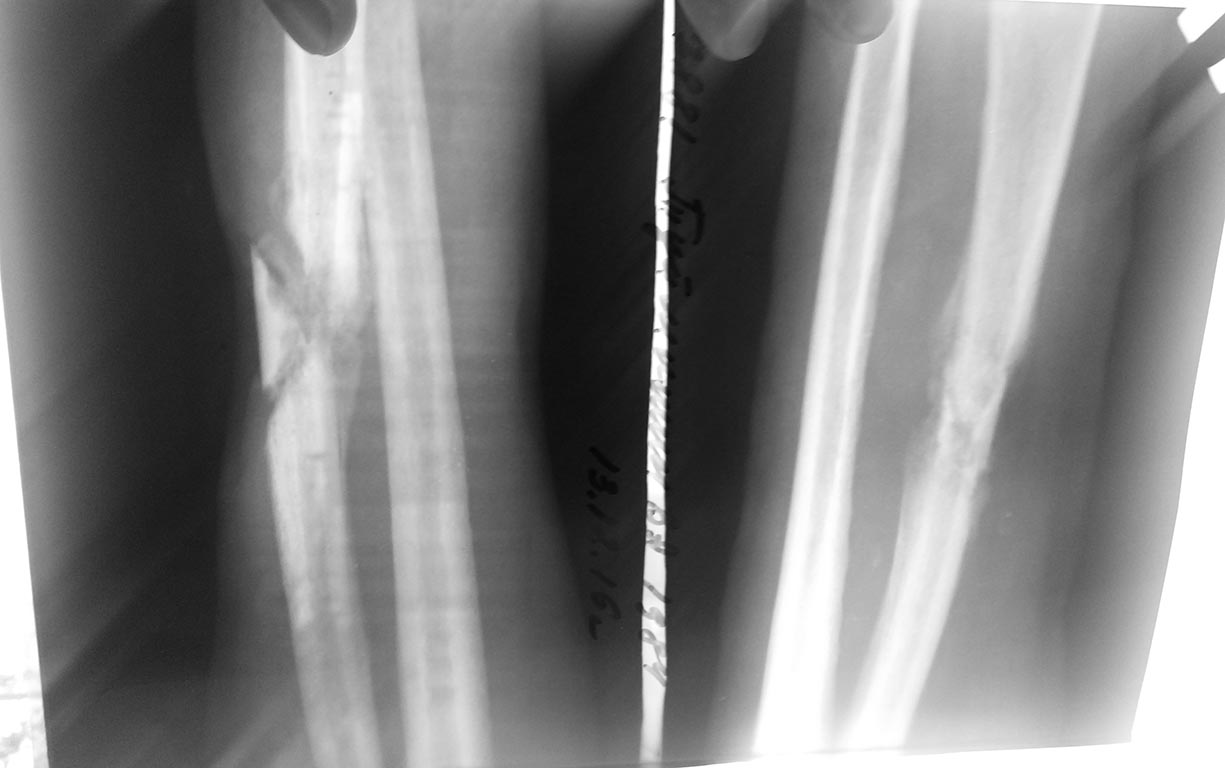

Больной 1984 г.р. 6 месяцев назад получил травму - удар высоковольтным током.

Лечился сам. Обратился в районную больницу и был направлен с диагнозом: инфицированная рана с/3 правго предплечья, остеомиелит лучевой кости. Дефект кожи размером 3.0х3.0см, гнойное отделяемое.

Тактика лечения?

Резицировать концы отломков далее АВФ?